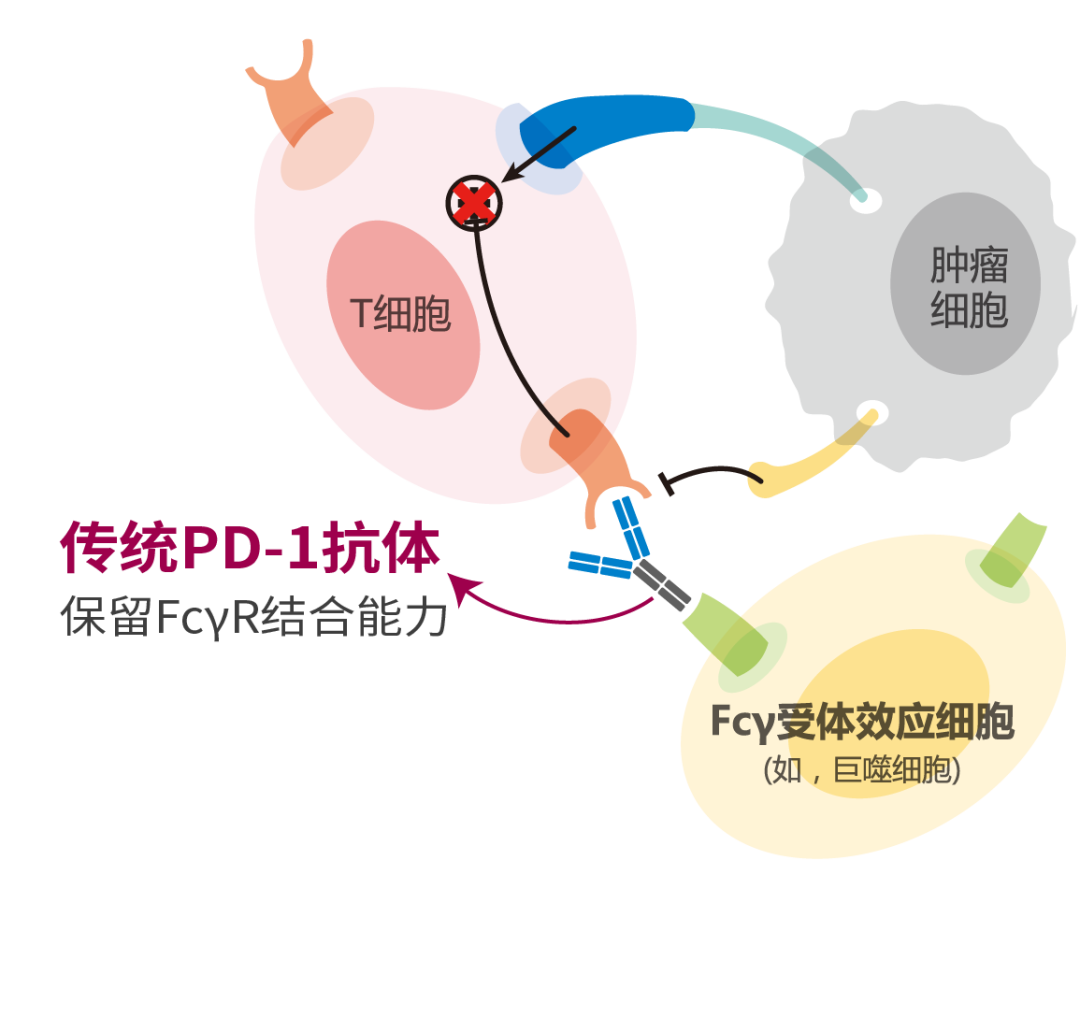

近年来,以PD-1/PD-L1免疫检查点抑制剂为代表的免疫治疗革命性地改变了众多肿瘤的治疗模式,其通过调动机体自身的免疫功能对肿瘤细胞进行杀伤,具有持久的疗效并能够明显改善预后,已成为当前最具潜力的抗肿瘤治疗方法,同时也为晚期NSCLC患者带来了更多的治疗选择,不断刷新晚期NSCLC患者的生存时间,将NSCLC的治疗获益提升至新的高度。

基于RATIONALE 307研究的成功探索,国家药品监督管理局(NMPA)已正式批准替雷利珠单抗用于晚期肺鳞癌一线治疗适应症,替雷利珠单抗也因此成为目前唯一有肺鳞癌适应症的国内自主研发PD-1单抗。基于RATIONALE 304研究数据,替雷利珠单抗联合化疗用于一线治疗非鳞状NSCLC患者的新适应症上市申请也已被NMPA正式受理,获批指日可待。替雷利珠单抗的获批为我国广大的肺癌患者带来了更多治疗选择,而更加可喜的是,替雷利珠单抗现已顺利纳入最新国家医保药品目录,意味着治疗门槛更低,药物的可及性更高,切实减轻了肿瘤患者的治疗负担。现阶段,替雷利珠单抗仍在积极探索肺癌领域的更多治疗可能,期待其能够不断积累循证医学证据及治疗经验,照亮晚期肺癌患者的人生“至暗时刻”!